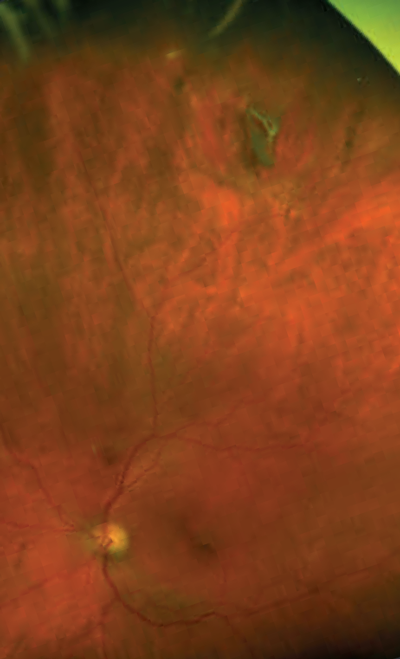

A 75-year-old gentleman was referred by his optician with marked left-sided macula pigmentation, querying wet age-related macular degeneration. Best corrected visual acuity (BCVA) in this eye was 0.1 LogMAR. The high-definition optical coherence tomography (OCT) scan showed an epiretinal membrane (ERM) but no signs of choroidal neovascular activity (Figure 1). When asked in more detail about any possible eye problems in the past, the patient recalled that he had had a vitreous haemorrhage in this eye some 13 years ago. On examination of the peripheral retina, a tear was found at one o’clock with a surrounding pigmented ring (Figure 2).

Figure 2: Wide-angle Optos fundus photography of the peripheral tear and the pigmented membrane

(same eye as Figure 1). Some eyelashes from the upper lid are depicted superiorly.